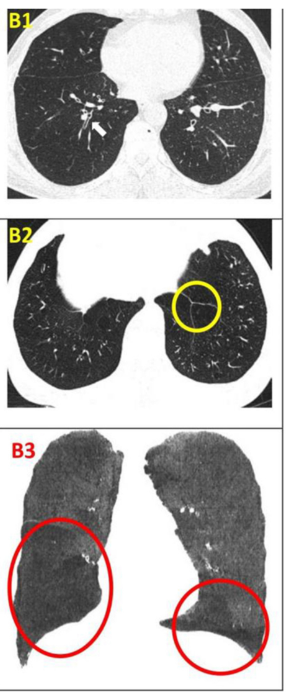

2021年4月28日,越南河內醫科大學在國際期刊《Respirology Case Reports》上發布了一篇《自體脂肪干細胞療法治療慢性阻塞性肺病:一例病例報告》的研究結果。【4】

運動能力和生活質量的變化:值得注意的是,接受ADSCs治療后6個月和12個月,患者的呼吸困難和生活質量均有所改善。6MWT在6個月和12個月的隨訪中有所增加。同時,CRP幾乎沒有變化。肺功能在12個月的隨訪中略有改善。該患者在一年的隨訪中沒有出現任何急性加重。

影像學檢查:隨訪12個月時,定量胸部CT掃描示患者吸入總肺容積略有增加,肺氣腫指數無明顯變化。支氣管壁厚度(WT)的變化以WT、壁面積(WA)及WA百分比(%WA)的減少,以及支氣管內徑(ID)和管腔面積(LA)的增大來評估。

干細胞治療一年后,雙肺RB1和RB10的WT均減少,LA增加(粗體指數)。